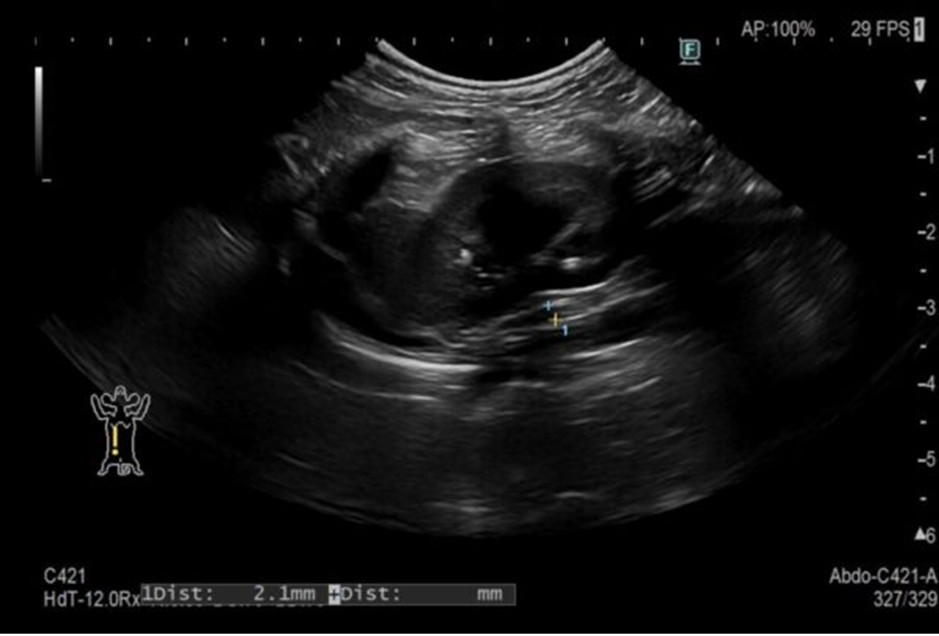

臨床徴候や身体検査などで椎間板ヘルニアを疑うことはできますが、確定診断には脊髄造影検査やCT・MRI検査等が必要になります。

当院での治療の流れとしては、臨床徴候からヘルニアが疑わしい場合はグレードが軽ければ内科治療で経過をみていきます。内科治療への反応が乏しく、痛みや麻痺が続く場合やグレードが重い場合はCT・MRI検査に進み、確定診断の後に外科手術を実施しています。手術後にはリハビリをすることで足の機能がしっかり戻る子が多いです。また、重度の麻痺で足の動きがなかなか戻らない症例でも、再生医療(脂肪肝細胞の投与)を併用することもできますので、お困りの方はお問い合わせください。